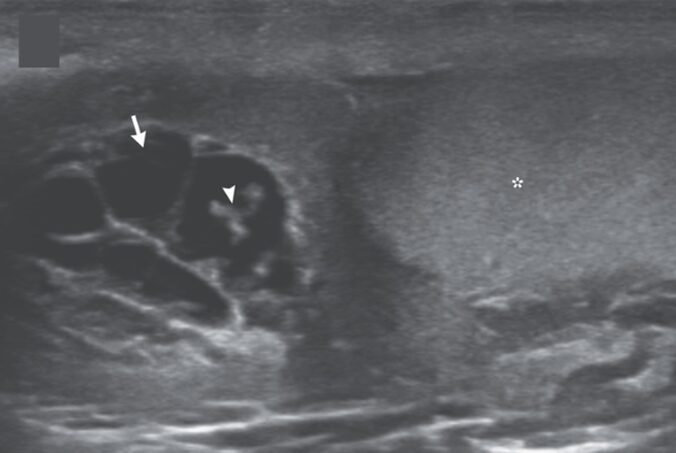

陰嚢超音波では右精巣(星印)および精巣上体の近くに索状構造物を認め、移動性があることが確認された。カラードップラーは陰性だった。

「フィラリアダンスサイン」として知られるリンパ性フィラリア症における所見と一致していた。

ダンスサインはリンパ管に侵入し、リンパ管の拡張と機能不全を引き起こす生きた虫のうねりを表している。